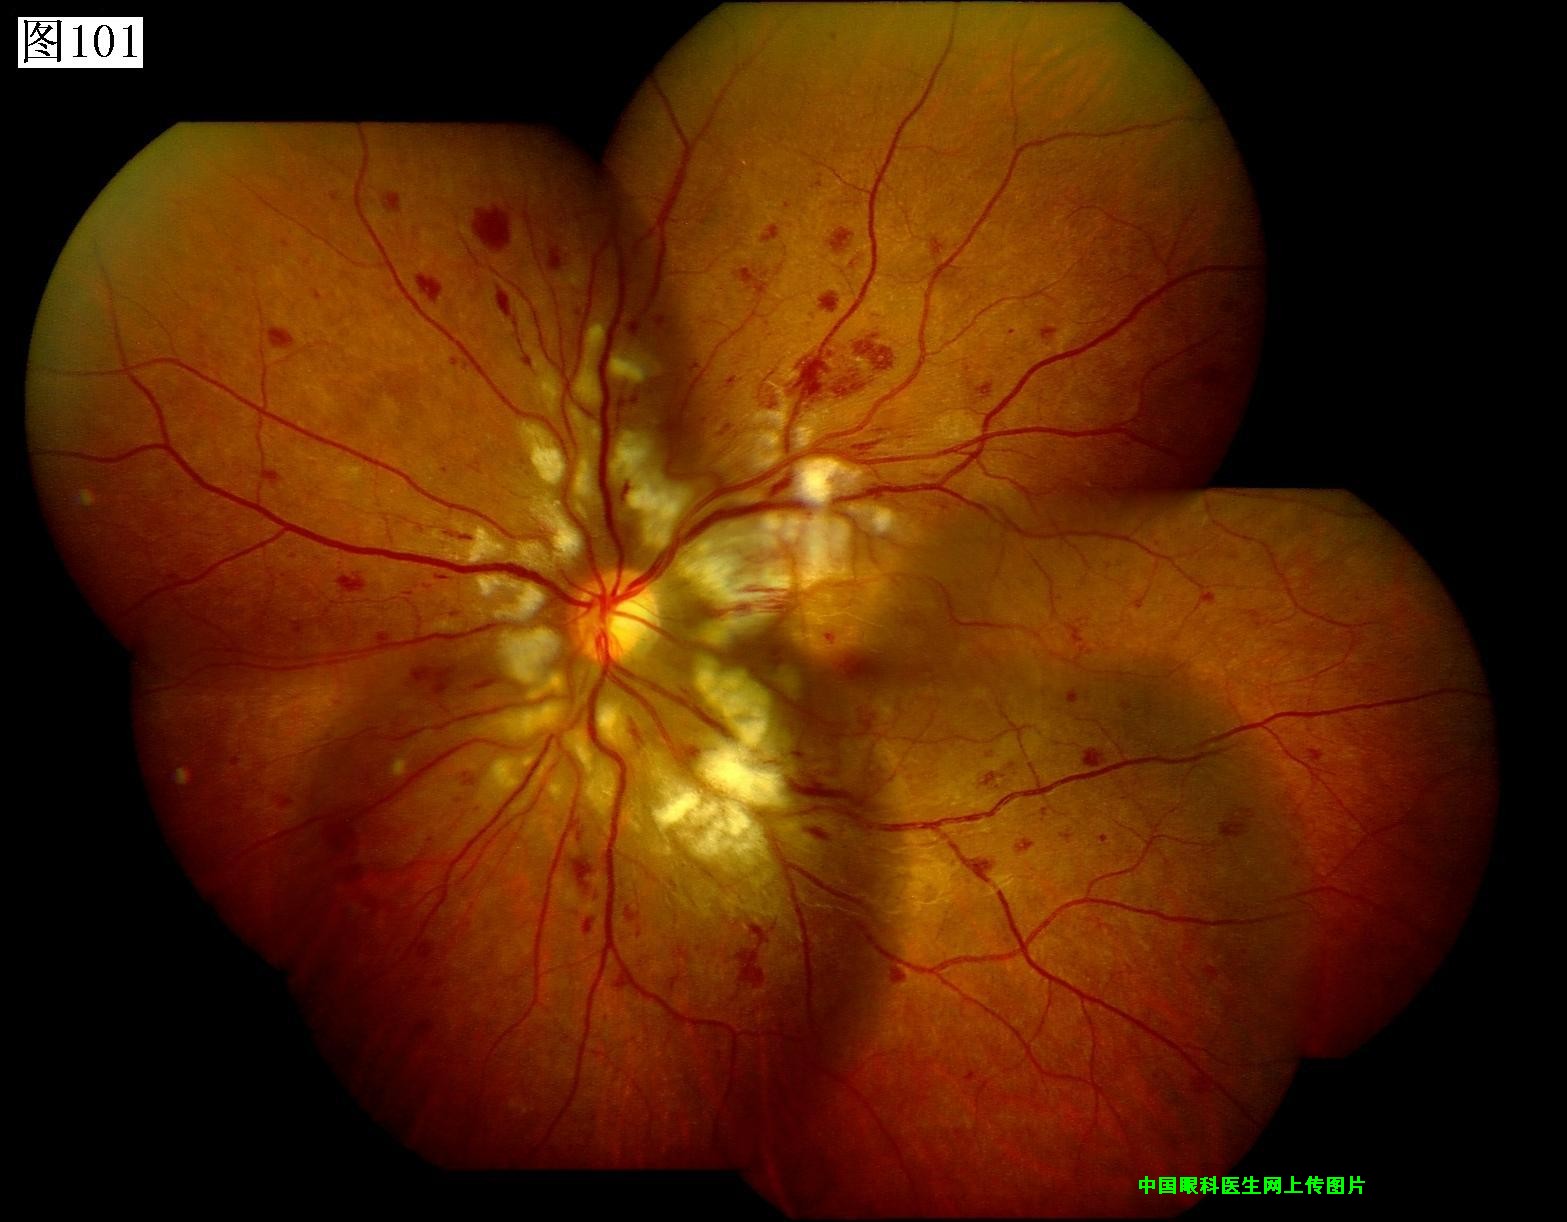

101 102 103 104